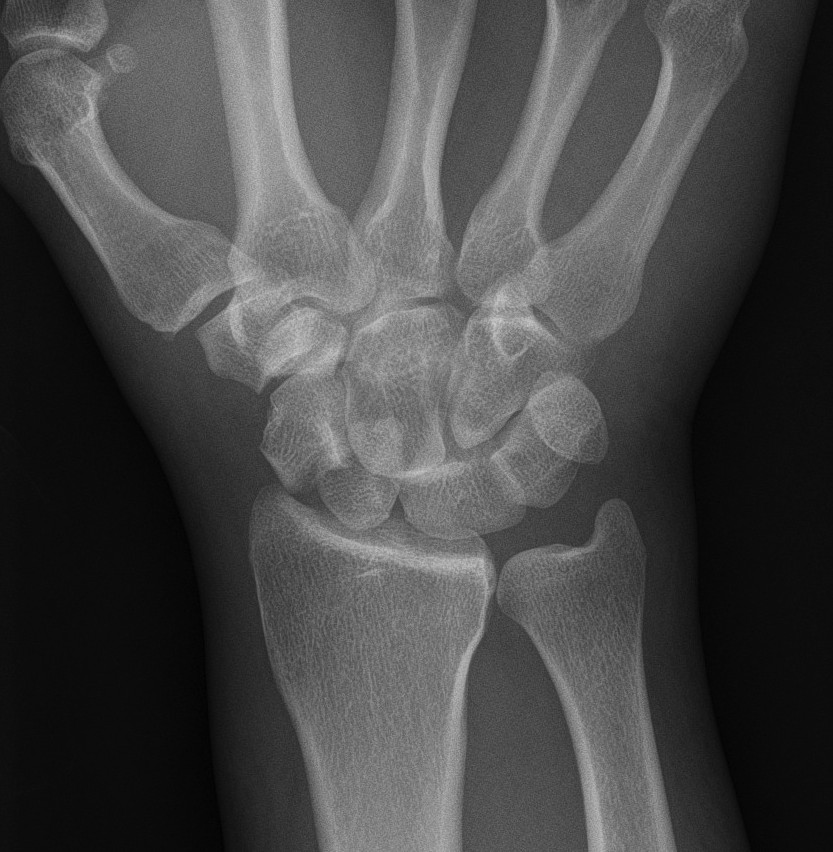

X-ray

Disruption of Gilula's 3 smooth carpal arcs

Progressive Injury

1. Capitate dorsal

- lunate remains with radius

- lunate looks triangular on AP

2. Lunate dislocates

- usually volar

2 main groups of injury

1. Dorsal trans-scaphoid dislocation

- 2/3 of cases

2. Dorsal perilunate dislocation

- 1/3 of cases